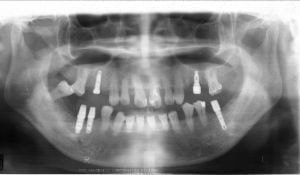

治療例2 (補綴処置+矯正)